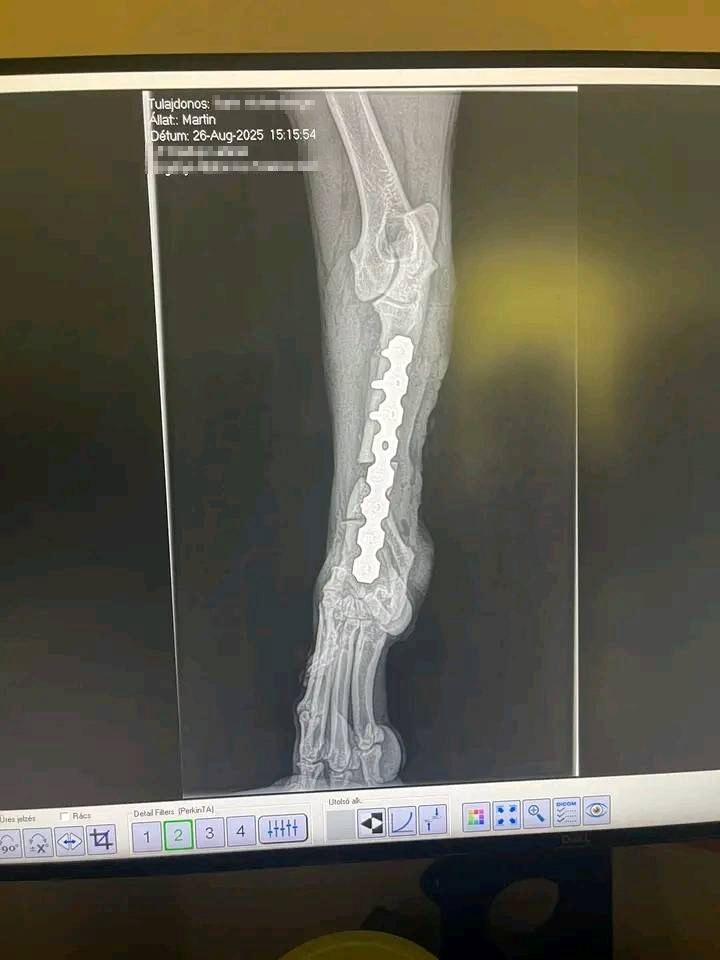

Die tierärztlichen Dokumente und Rechnungen nennen den Namen Karin Hohenberger.

In ihrem öffentlichen Facebook- oder Instagram-Profil finden sich zahlreiche Posts über ihren Rottweiler „Martin“ – unter anderem zu seiner OP und Genesung:

➡️ Das spricht eindeutig dafür, dass Karin Hohenberger die rechtmäßige Halterin ist, die Martin durch die medizinische Versorgung begleitet und öffentlich dokumentiert hat.

Die Bilder (von mir anonymisiert)

- Der Hund ist kein Dobermann, sondern eindeutig ein Rottweiler (laut Unterlagen und äußerlich).

| Rasse | Dobermann (falsch) | Rottweiler (nach Dokumenten & Erscheinung) |

- Der Hund auf den Bildern heißt Martin, ist ein Rottweiler und wird von Karin Hohenberger versorgt.